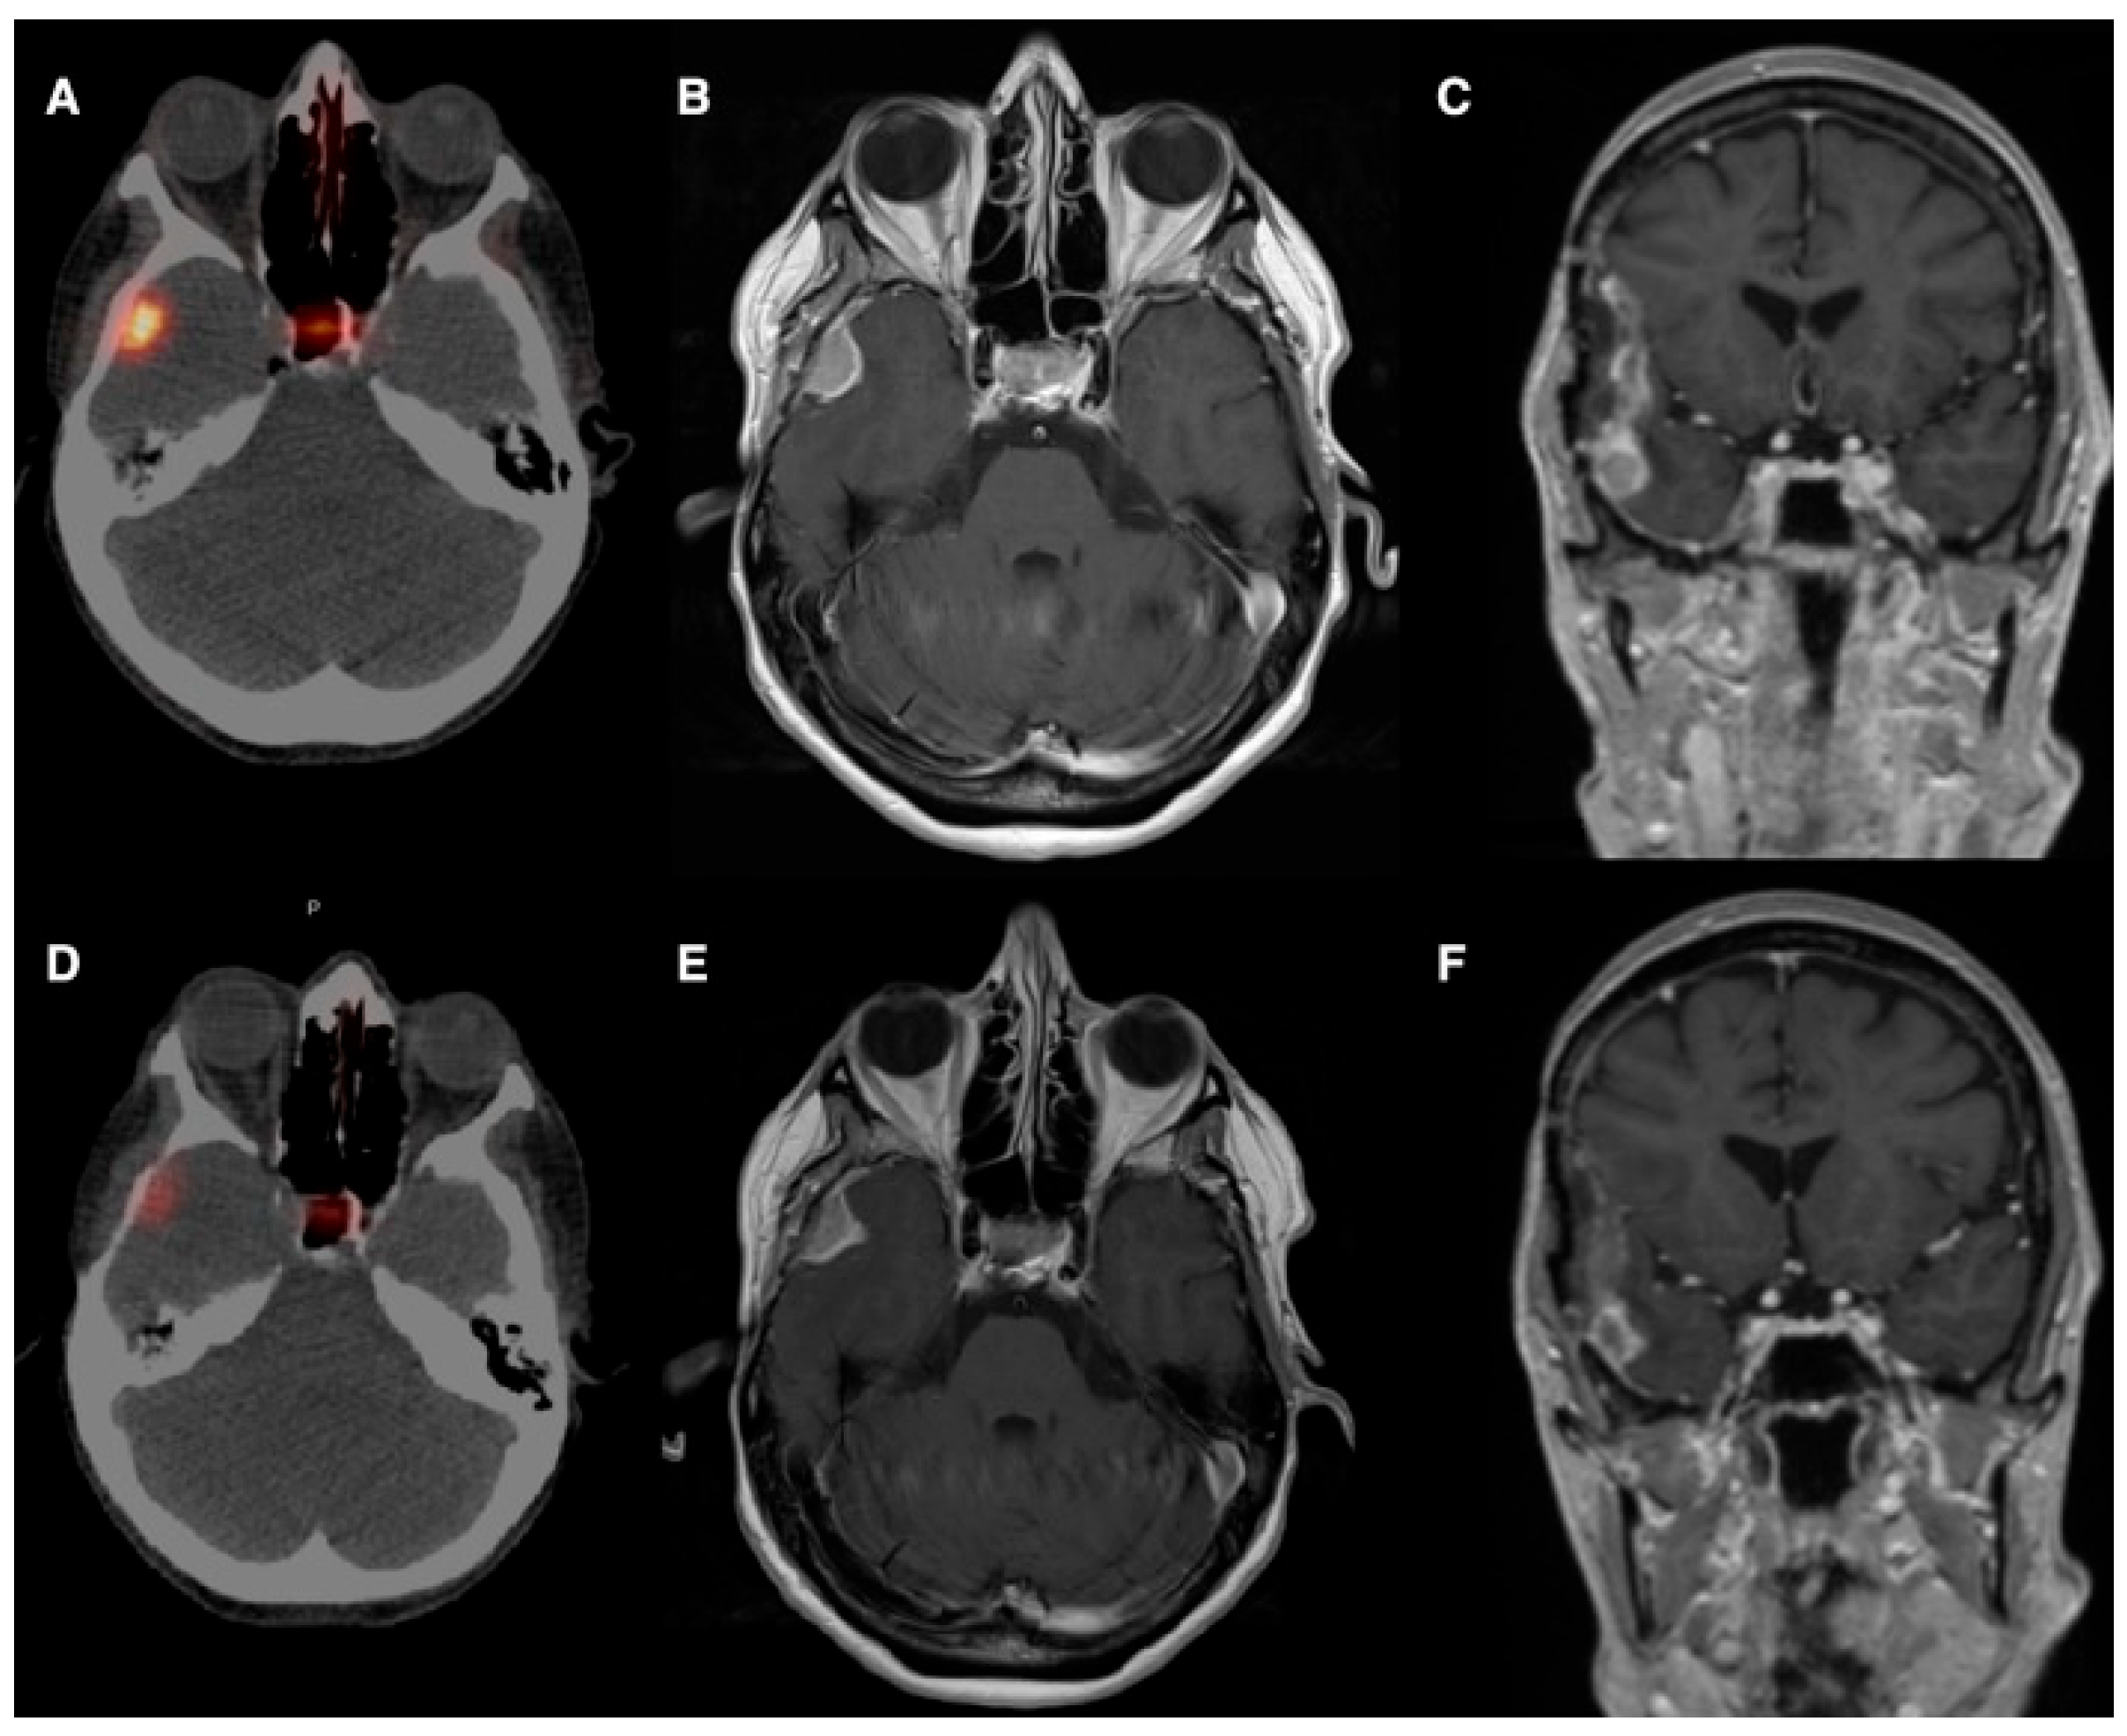

The first experience by Braat et al. [19] provided the rationale for selective vascular delivery in meningioma. They reported the case of a 54-year-old woman with a recurrent right-temporal WHO grade II meningioma, refractory to three surgical resections and seven courses of radiotherapy, presenting with frequent focal seizures and recurrent status epilepticus. As the tumor was deemed unresectable and further external radiotherapy unsafe, 68Ga-DOTATOC PET/CT demonstrated high SSTR2 expression, prompting treatment with PRRT. An initial intravenous administration of 7.4 GBq 177Lu-DOTATATE resulted in low tumor uptake and an estimated absorbed dose of approximately 4.6 Gy. Subsequently, selective IA administration via the right external carotid artery led to an 11-fold increase in tumor uptake, achieving an estimated absorbed dose of 51 Gy per cycle. After four PRRT cycles (one intravenous and three IA; cumulative activity 29.6 GBq), the estimated total tumor absorbed dose reached 154 Gy. Follow-up PET/CT and MRI demonstrated a marked reduction in SSTR2 expression, central tumor necrosis, and a partial radiological response. Clinically, severe seizures resolved completely, while focal sensory seizures decreased from daily episodes to 3–4 per week, with stable control and sustained partial response at 10-month follow-up and no relevant treatment-related toxicity (Figure 2 and Figure 3).

Figure 3. (A) Post-treatment 177Lu-HA-DOTATATE scan after intravenous administration shows only faint radiotracer uptake in the meningioma. (B,C). Anterior and lateral digital subtraction angiography during selective injection in the right external carotid artery (middle meningeal branch), just proximal to the parotid artery origin, demonstrates a clear tumor blush (white arrows). This position was selected because an additional feeding branch arose from the parotid artery. (D). After intra-arterial administration, the post-treatment 177Lu-HA-DOTATATE scan shows a marked increase in radiotracer uptake, with quantification demonstrating an approximately 11-fold enhancement. Reprinted from [19] under a creative commons attribution 4.0 international license (http://creativecommons.org/licenses/by/4.0/, accessed on 31 October 2025). No changes were made.